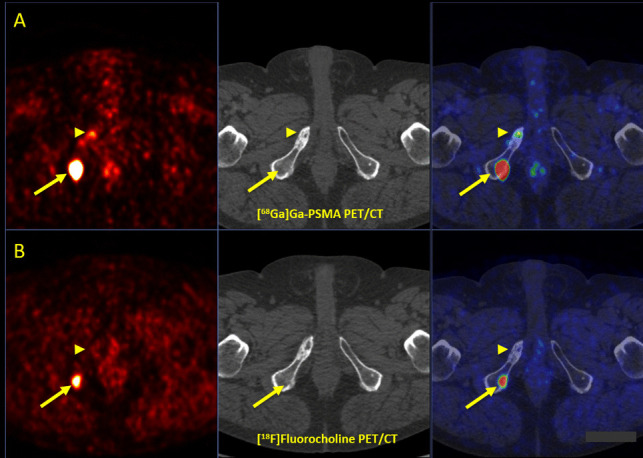

Results: Both imaging modalities detected 136 total malignant lesions. [68Ga]Ga-PSMA-11 and [18F]FCH PET/CT detected 125 and 60 lesions with a sensitivity of 96% and 48%, respectively. Tumor-to-background ratios and semi-quantitative PET parameters on [68Ga]Ga-PSMA-11 were significantly higher in 54 (41.2%) tracer-avid congruent lesions detected on both imaging modalities. [68Ga]Ga-PSMA-11 PET/CT exclusively detected 71 (52.2%) lesions, while 6 (4.4%) lesions were solely seen on [18F]FCH PET/CT. [68Ga]Ga-PSMA-11 and [18F]FCH PET/CT were positive in 35/46 (76%) and 26/46 (57%) patients, respectively. PET/CT imaging led to a major treatment change in 4 (8.7%) patients, of which [18F]FCH PET/CT had superior impact in one patient.

Conclusions: [68Ga]Ga-PSMA-11 PET/CT revealed superior diagnostic performance to [18F]FCH PET/CT in patients with recurrent PCa, specifically with very low PSA levels ≤ 1 ng/ml. Moreover, it led to more accurate staging and clinical management of the disease. [18F]FCH PET/CT may play a complementary role in rare, select high-risk cases with negative [68Ga]Ga-PSMA-11 PET/CT and ongoing ADT.